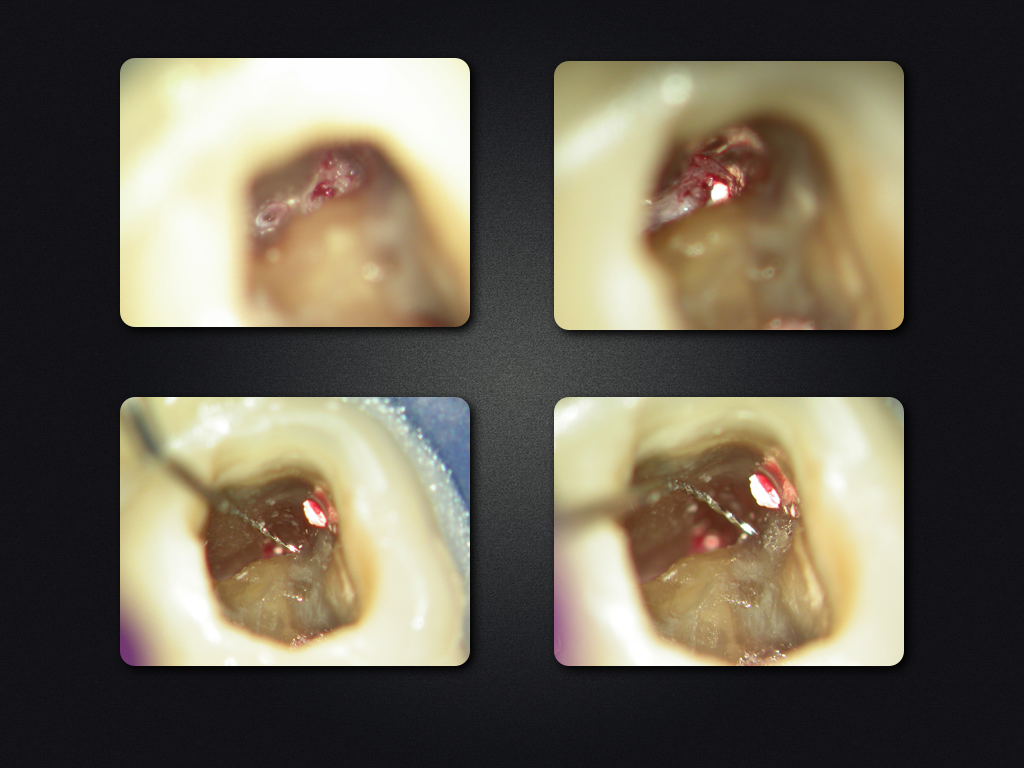

2D vs. 3D (XXVI)